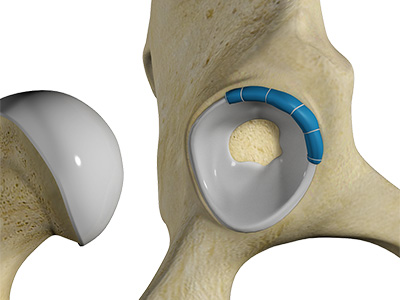

The hip joint is the junction where the hip joins the leg to the trunk of the body. It is comprised of two bones: the thigh bone or femur and the pelvis which is made up of three bones called ilium, ischium, and pubis. The ball of the hip joint is made by the femoral head while the socket is formed by the acetabulum. The Acetabulum is a deep, circular socket formed on the outer edge of the pelvis by the union of three bones: ilium, ischium, and pubis. The lower part of the ilium is attached by the pubis while the ischium is considerably behind the pubis. The stability of the hip is provided by the joint capsule or acetabulum and the muscles and ligaments which surround and support the hip joint.

The head of the femur rotates and glides within the acetabulum. A fibrocartilagenous lining called the labrum is attached to the acetabulum and further increases the depth of the socket.

- Acetabular labrum: The labrum is a fibrous cartilage ring which lines the acetabular socket. It deepens the cavity, increasing the stability and strength of the hip joint.